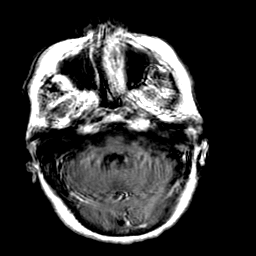

Creutzfeld-Jakob disease: gadolinium enchanced T1-Weighted MR -- Slice #5

[Home][Help][Clinical] Slice 5